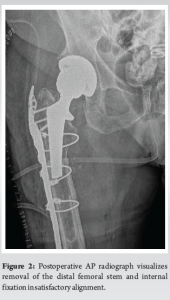

The surgical approach began with an incision on the lateral aspect of the right leg, with careful dissection through the iliotibial band, which was incised longitudinally. A soft vastus approach to the femoral shaft was utilized, reflecting the vastus lateralis in an L-shaped flap. During the procedure, a transverse fracture of the right proximal femur was discovered at the subtrochanteric region, which involved the cylindrical stem. Both the proximal and distal portions of the femoral stem were found to be well-fixed with excellent bone ingrowth. Due to the significant morbidity that would result from removing the proximal portion of the femoral stem, the decision was made to only remove the distal portion. A cylindrical trephine was used to core out the distal segment of the stem, with minimal bone loss. In addition, a 15 mm sliver of bone was removed from the distal portion of the proximal femoral stem, which was intussuscepted into the intramedullary canal of the distal femur. This achieved an excellent apposition of the bony surfaces while maintaining rotational alignment. A long periprosthetic proximal femoral plate with a trochanteric extension was placed along the lateral cortex of the femur to span the fracture site. Subsequently, a cortical strut allograft was applied along the posterior aspect of the femur. Proximal fixation was achieved using multiple circumferential cables, as well as both non-locking and locking screws with compression across the fracture site, provisionally maintained using a clamp. Distal fixation was reinforced with additional bicortical screws and cables. Intraoperative radiographs demonstrated optimal reduction of the fracture, with the femoral stem tip positioned below the fracture site (Fig. 2). The lateral proximal femoral plate spanned the fracture site at over 1.5 times the canal diameter, in accordance with conventional recommendations for bypassing the fracture, ensuring stability and proper alignment. Postoperatively, the patient was made toe-touch weight-bearing on the right leg for the first 6 weeks, with progressive weight bearing as tolerated during the following 6 weeks. Physical therapy continued throughout this period (Fig. 3).